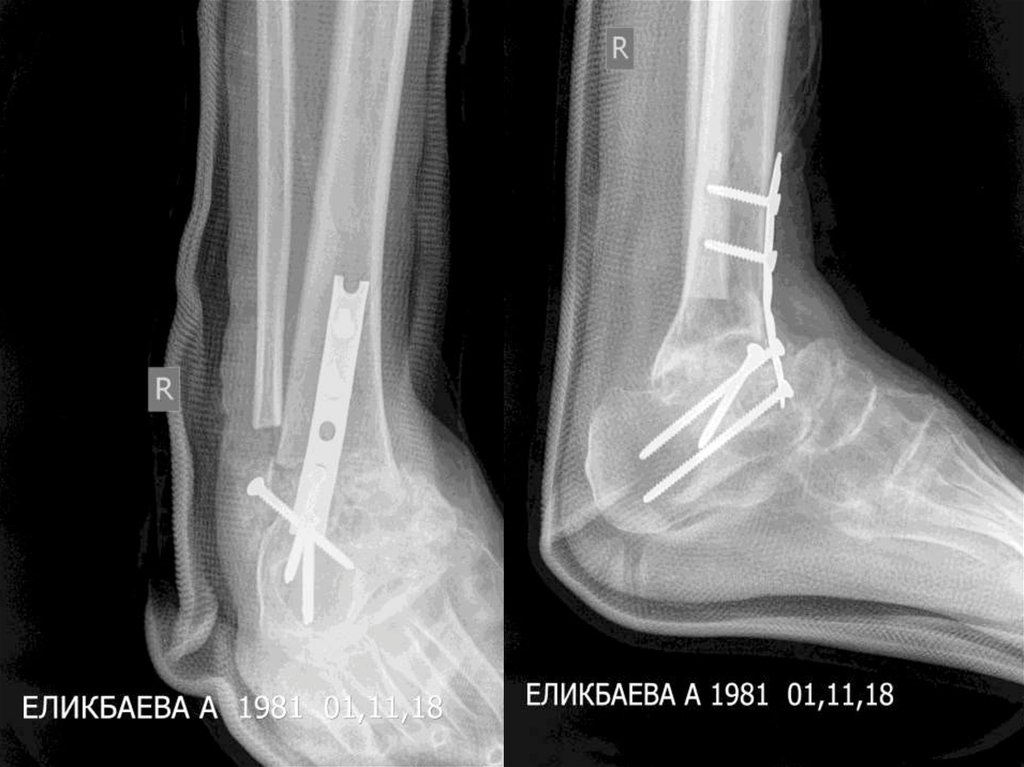

11. ЕЛИКБАЕВА АЛИЯ АБДИКАДЫРОВНА     12.10.1981 (37жас)

ЕЛИКБАЕВА АЛИЯ

АБДИКАДЫРОВНА 12.10.1981

(37жас)

Диагноз: оң тобық буынының артрозы.

Операция: оң тобық буынының артродезі.